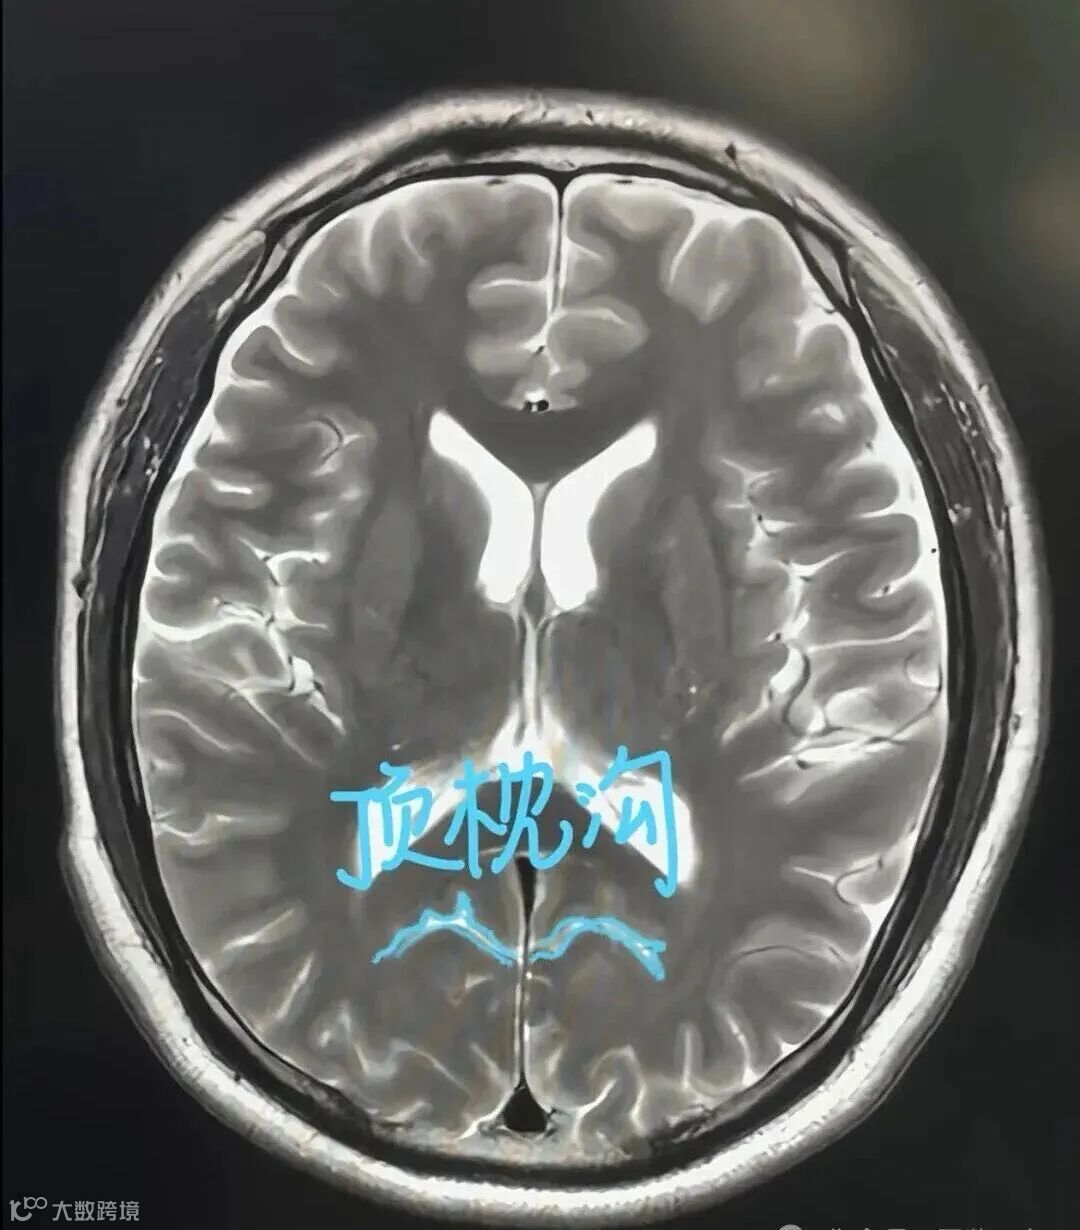

顶枕沟:枕叶与顶叶的分界,位于大脑半球内侧面的后部